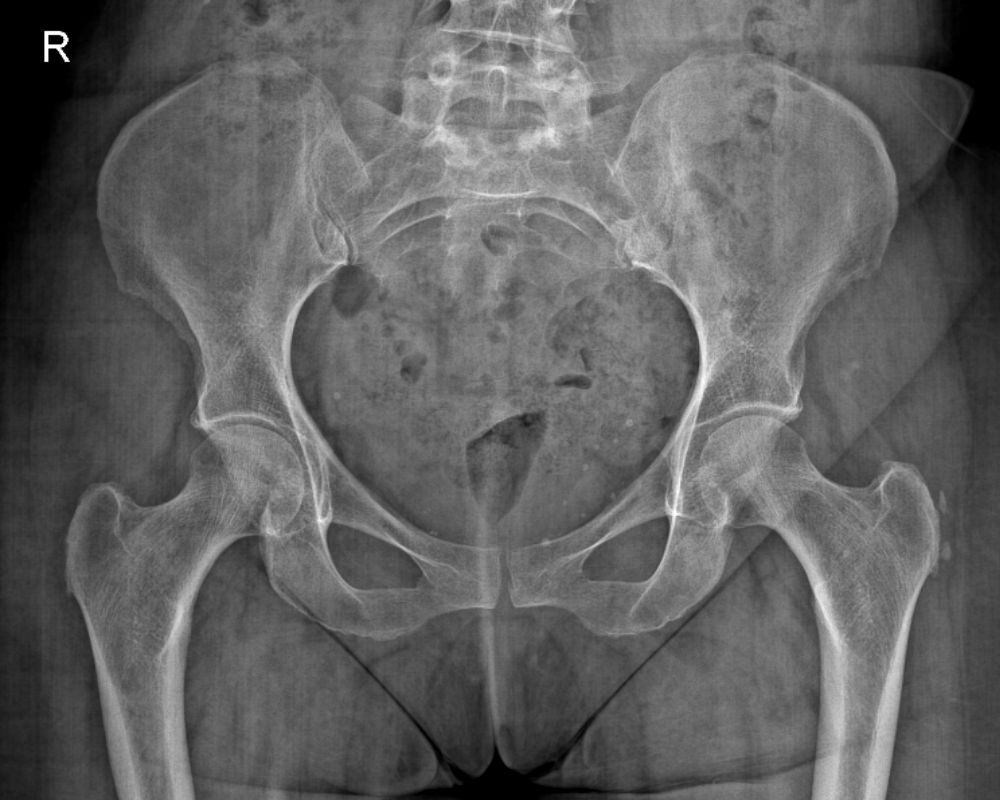

As Radiografias dos ossos e articulações necessitam posicionamentos adequados e específicos para cada região.